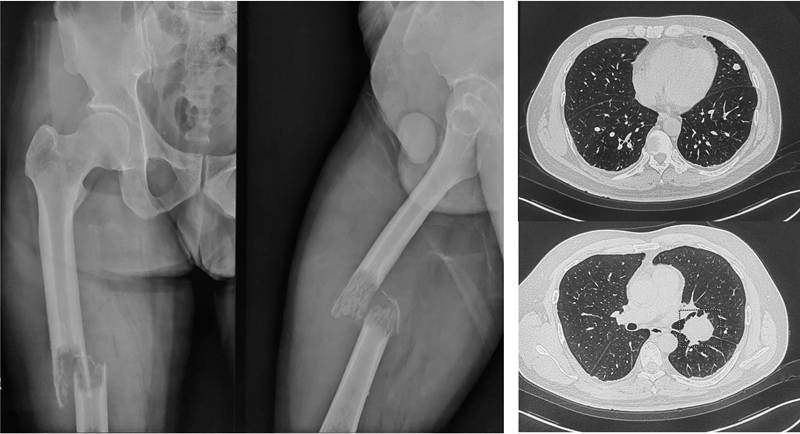

病例三

男性,51岁。因右股骨干病理性骨折入院。患者于10年前行右肾恶性肿瘤切除术。入院诊断为右股骨干肾癌转移并病理性骨折,郭世炳教授骨肿瘤团队实施了瘤段切除3D打印节段性假体重建股骨干术。术后恢复较好,2周下地扶拐行走。

图3a 男,51岁,右肾癌切除术后10年股骨转移并病理性骨折,肺内多发转移

图3b 术后X正侧位

①肾癌50%初诊时存在骨转移,50%发生在肾癌切除术后,骨转移表现为纯溶骨破坏,病理性骨折发生率高。放疗和化疗不敏感,手术是主要治疗方式,可显著延长患者生存期,整块切除可明显降低病灶内手术复发率,抗血管生成靶向药物明显延长生存期(VEGFR-TKI)。

②本例患者尽管有肺转移,术后病理基因检测表明,具有强临床意义的变异(Ⅰ类变异)未发现相关突变位点,但是具有潜在临床意义的变异(Ⅱ类变异)VHL突变,可用依维莫司药物治疗。